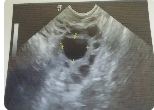

降調(diào)的作用主要就是為了有效的促排時避免大大小小卵泡出現(xiàn),提升卵泡質(zhì)量。而直接促排就是沒有進(jìn)行降調(diào),可以很好的增加卵泡數(shù)量,確保取出更多的卵子;

降調(diào)為了獲得更多成熟的卵泡,只需要打一針,而卵巢功能不好就需要降調(diào),這樣才能避免出現(xiàn)卵巢過度刺激癥,也能避免頭暈、惡心的癥狀泡的數(shù)量;

之所以有的患者需要降調(diào)有需要進(jìn)行促排,是因為促排卵是使用藥物促使多個卵泡同時生長,這樣會擾亂下丘腦-垂體-卵巢軸的調(diào)控機制。這種情況可能會導(dǎo)致排卵提前或還沒排出卵子,卵泡就已經(jīng)變成了黃體。很多時候為了避免這種情況發(fā)生,是需要在前期使用降調(diào)節(jié)治療,采用藥物干預(yù)下丘腦-垂體-卵巢軸的調(diào)節(jié)作用。前期降調(diào)節(jié)可以幫助卵泡生長更加容易被醫(yī)生控制,爭取獲得多個同步發(fā)育的成熟卵泡,并且盡量保證卵細(xì)胞質(zhì)量。